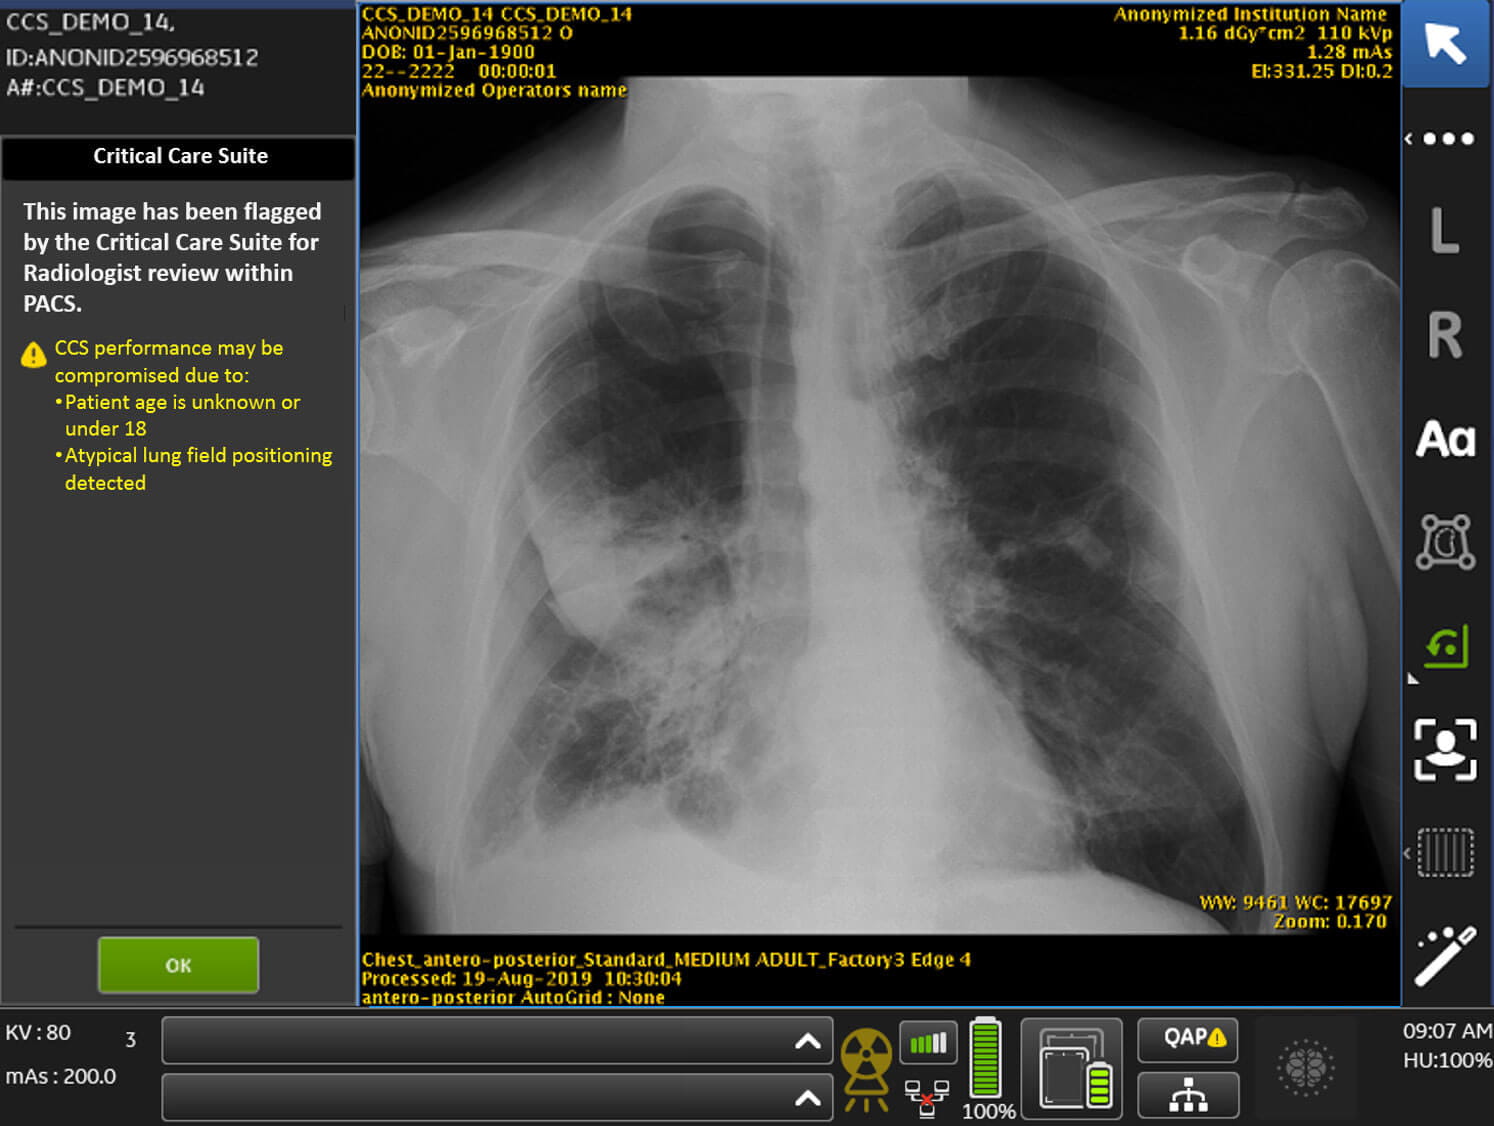

Critical Care Suite Interface Critical Care Suite interface.

Radiologists at UH Cleveland Medical Center read dozens of images every day. This process takes several hours. To assist them, GEHC’s Critical Care Suite software acts as artificial intelligence on board the Optima XR240amx mobile x-ray unit. Once a chest x-ray is taken, it recognizes if a patient has a collapsed lung and flags the image for immediate reading, setting the patient on a rapid path to treatment.